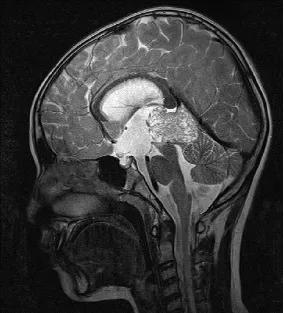

一、松果体区肿瘤的病理类型

二、松果体区肿瘤的临床表现

1.中脑导水管受压→梗阻性脑积水→颅内压增高

2.上丘破坏→双眼上视不能(Parinaud综合征)

3.下丘损害→听力障碍

4.小脑受压→共济失调